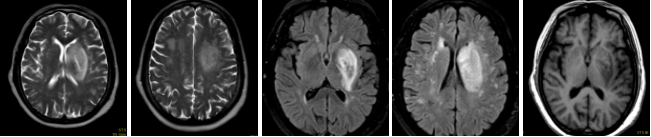

病例二 男,69歲, 于1月前無(wú)明顯誘因出現(xiàn)右上肢麻木不適, 此癥狀間斷存在, 持續(xù)數(shù)分鐘, 活 動(dòng)后好轉(zhuǎn)。 于1周前上述癥狀持續(xù)存在, 活動(dòng)后未見(jiàn)好轉(zhuǎn)入院檢查。

根據(jù)左側(cè)頸內(nèi)動(dòng)脈閉塞的長(zhǎng)度、形態(tài)以及側(cè)枝循環(huán)代償情況,考慮左側(cè)頸內(nèi)動(dòng)脈為慢性閉塞。

腦血流灌注圖可見(jiàn)CBF輕微下降,CBV略升高,MTT升高 ,TTP升高明顯。

640層寬體探測(cè)器CT灌注聯(lián)合CTA檢查,可在CTA掃描發(fā)現(xiàn)血管異常時(shí), 應(yīng)用CTP協(xié)助發(fā)現(xiàn)異常灌注區(qū), 對(duì)缺血的程度及代償情況進(jìn)行評(píng)估; 對(duì)照多時(shí)相血管CTA,找到責(zé)任血管, 評(píng) 價(jià)側(cè)支循環(huán); 兩者從形態(tài)學(xué)及功能學(xué)多方面對(duì)缺血性腦病進(jìn)行評(píng)估, 對(duì)臨床個(gè)性化診斷和治療具有重要指導(dǎo)意義。